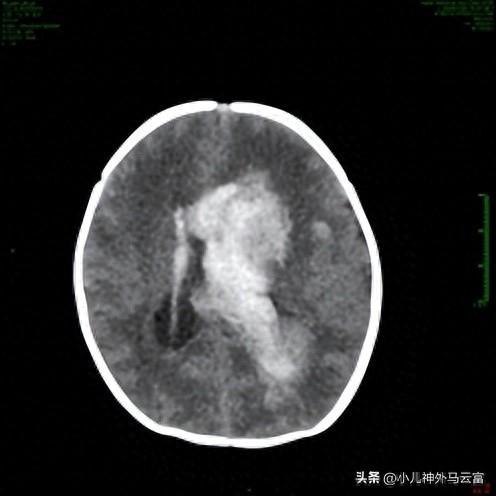

患兒小孔,因有宮內窘迫,出生後間斷抽搐1天,CT提示雙側額葉血腫;雙側側腦室及三腦室積血;大腦鐮下疝。

提示:1.重度顱內出血(非創傷性)2.大腦鐮下疝[扣帶回疝]3.凝血功能障礙4.低出生體重兒5.早產兒

7月28日CT提示顱內出血